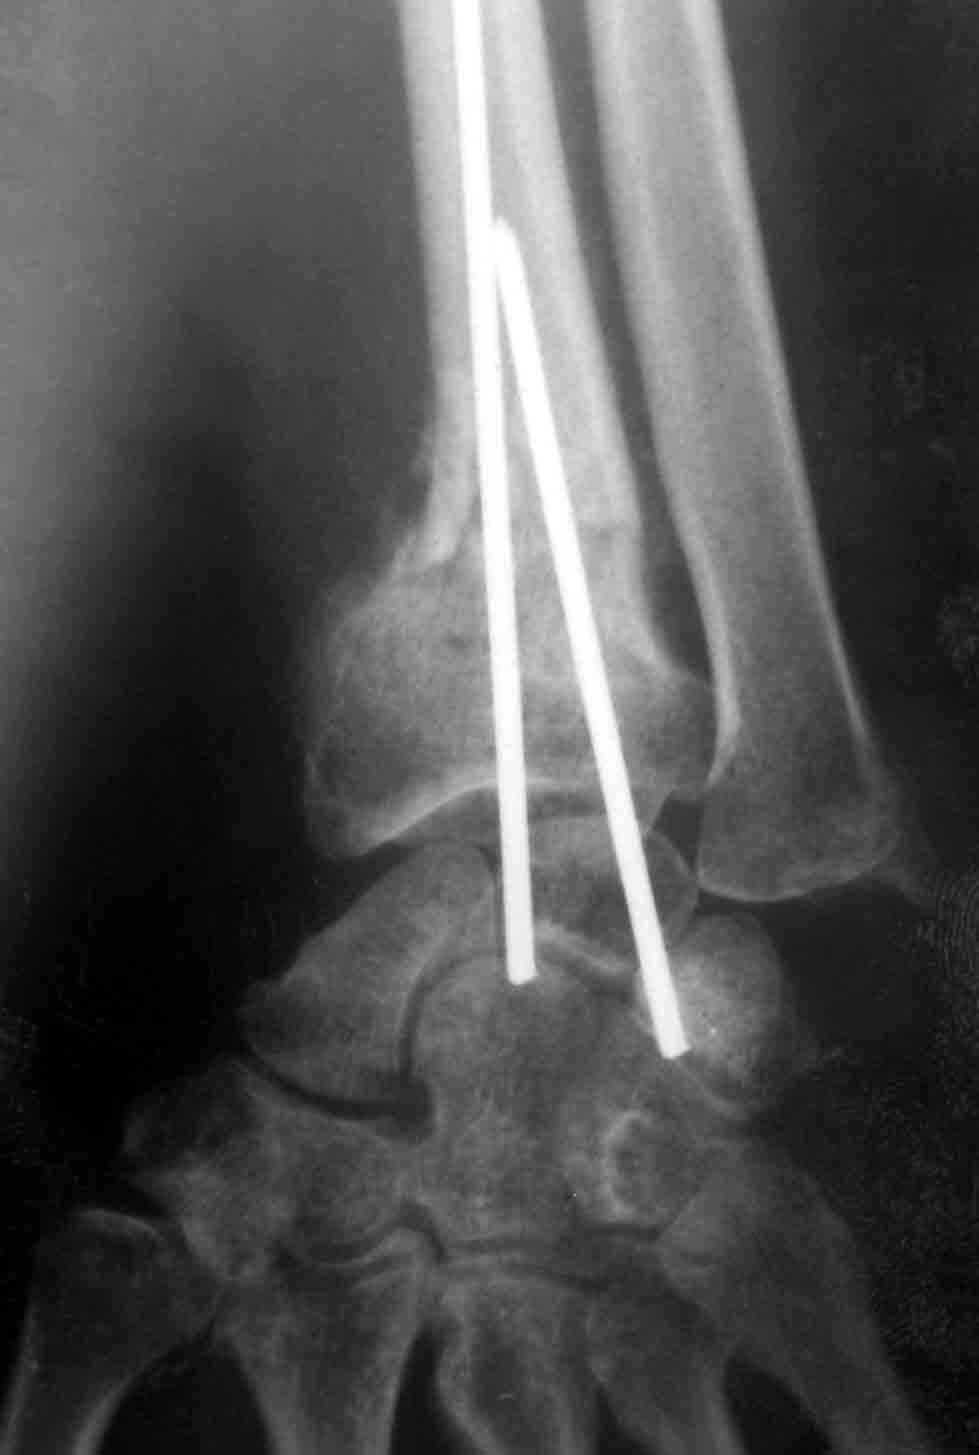

После 4 месячного лечения в поликлиниках города 43 летняя пациентка, экономист поступила с грубой деформацией правого предплечья, контрактурой пальцев и невритом срединного нерва средней степени тяжести. После неплохой репозиции чрезсуставного трехфрагментарного перелома луча месяц провела в гипсе без рентгенконтроля. После снятия повязки ввиду лучевой девиации была предпринята какая-то остеотомия без костной пластики, деформация лишь усугубилась, головка локтя в вывихе. Учитывая молодой возраст в моих планах укорачивающая остеотомия локтевой кости, корригирующая остеотомия луча( перелом там похоже не сросся)для восстановления угловых соотношений в суставе с заполнением дефекта кости материалом из локтевой и коллапаном. Локтевая подлежит фиксации АО пластиной, лучевая, скорее всего, обойдется без фиксации. В моей практике ранее были остеотомии луча, удаления головки локтевой кости у престарелых, но укорачивающих остеотомий не производил. Кто имеет опыт подобных операций, поделитесь, понимаю, что необходим невролиз медиануса, но третий разрез в этой зоне не хочется выполнять. На англоязычных сайтах много материала по подобным случаям, на отечественных практически ничего

Прилагаю профильный снимок, на нем видно несрастание линии неудачной остеотомии. Если во время операции будет достаточно материала из локтевой для сохранения коррекции угла эпифиза луча и самокомпрессия удержит трансплантат попробую обойтись без дополнительной пластины. У молодых субъектов мне удавалось полностью исправить деформации\ менее тяжелые\ кортикотомией и введением клиновидного трансплантата из крыла подвздошной кости. Главное было правильно рассчитать линию и угол остеотомии, самокомпрессия была достаточной для консолидации в течение 5 недель. По поводу ЧКДО-больная категорически отказалась. Операция Sauve Kapandji с укорочением локтевой кости, но без удаления хряща луче-локтевого сустава мне видится предпочтительней удаления головки локтевой. Пациентка- экономист по профессии и работает мышью и клавой, так что после удаления дистального локтя неизбежны последующие проблемы в локтевом суставе, а так при восстановлении градусов 25-30 пронации-супинации сможет трудиться. Стоит ли одномоментно мобилизовать срединный нерв в карпальном канале?

Спасибо всем коллегам за полезные советы. На АВФ больную уговорить не смог, т.к. она пожелала в гипсовой повязке выйти на работу\ капитализм на дворе\. Сделал укорочивающую остеотомию с удалением до 13 мм блока ульны осциллирующей пилой и после адапатации с фиксацией пластиной уже рука выглядела симпатичнее. На уровне прежней остеотомии псевдоартроз освежил с удалением остеоидной ткани и косой кортикотомией коррегировал смещение эпифиза. В дефект насыпал коллапан, кортикал плотно закрылся резецированным из ульны фрагментом. Фиксация пластиной была бы предпочтительнее гипсовой, но состояние кожи с рубцами и отеком остановило меня. Рентгеноскопия на столе показала хорошую коррекцию, снимки выложу позднее. Через пять дней появилась незначительная динамика неврита срединного нерва.